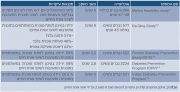

| 14:00, 23 בפברואר 2016 | Takeda777.png (קובץ) |  |

94 קילו־בייטים | דנה לוי | 1 | |